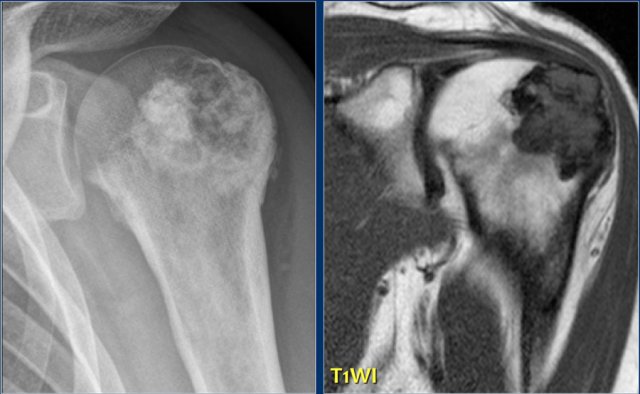

Chondrosarcoma in humeral head and sternum Chondrosarcoma in humeral head and sternum

Here two other lesions in different patients that proved to be chondrosarcoma.

The sclerotic lesion in the humeral head could very well be a benign enchondroma based on the imaging findings.

Symptoms are usually absent, however, in adult patients with a chondroid lesion in a long bone, particularly of larger size, always consider low-grade chondrosarcoma.